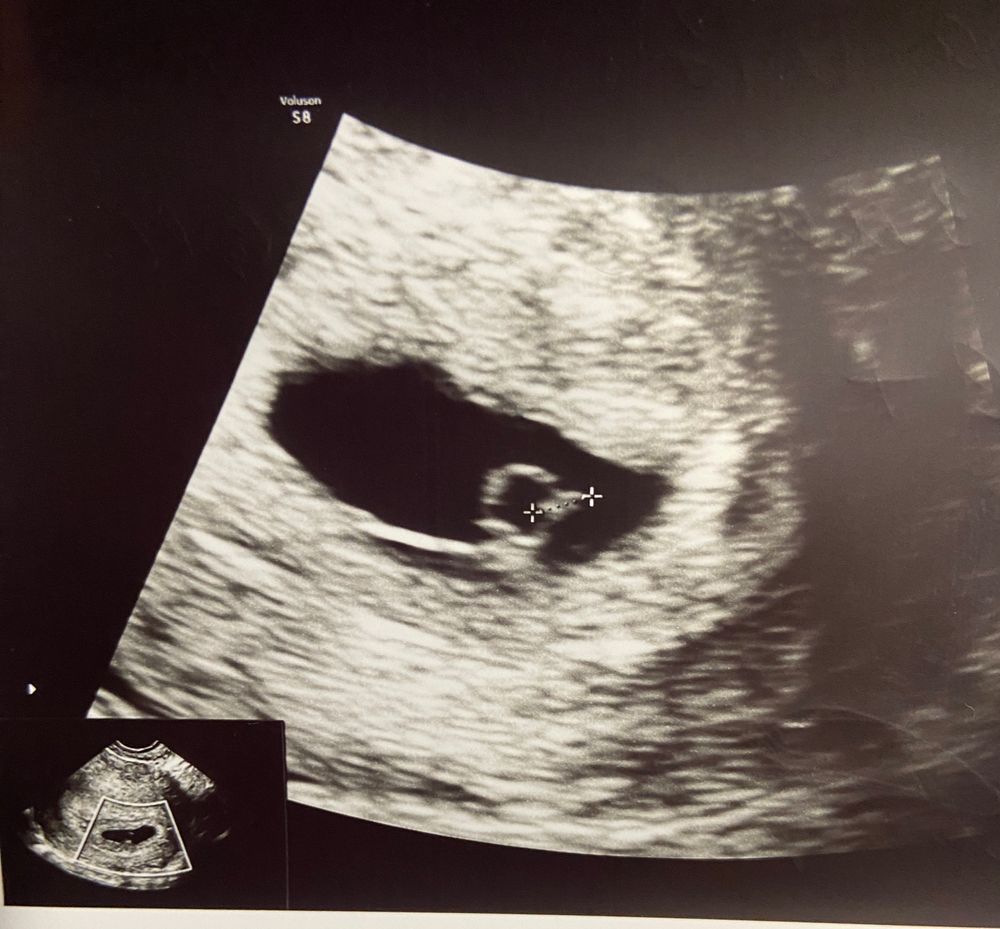

5+6 недель, подглядели немножко ☺️

Нам 5 недель и 6 дней по акушерскому.

УЗИ: ну во-первых мы в матке ☺️ во-вторых ктр 3 мм, и ЧСС + 🥰 срок по узи 5+1🤗

Все ли хорошо? Г сказала, что все хорошо,